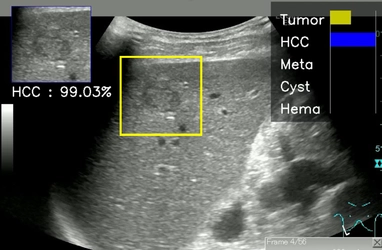

世界初!熟練医を上回る精度の肝腫瘤画像診断AIを開発 AIによる超音波診断の実用化に大きな期待

2022-02-28 15:00

学校法人近畿大学